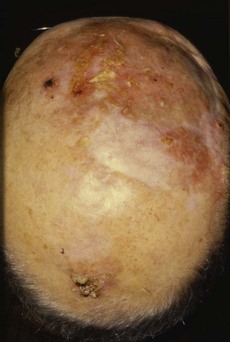

Hair loss (alopecia) can be total or partial (Fig. 4.14):

Fig. 4.14 Hair disorders.

(A) Male-pattern baldness with hair loss from the temples and vertex of the scalp. (B) Alopecia areata with ‘exclamation mark’ hairs, which taper as they approach the skin. (C) Scalp ringworm with secondary bacterial infection and localised hair loss.

• Scarring alopecia. Burns, severe infections, e.g. herpes zoster, lichen planus and SLE, may permanently scar the scalp with permanent hair loss.